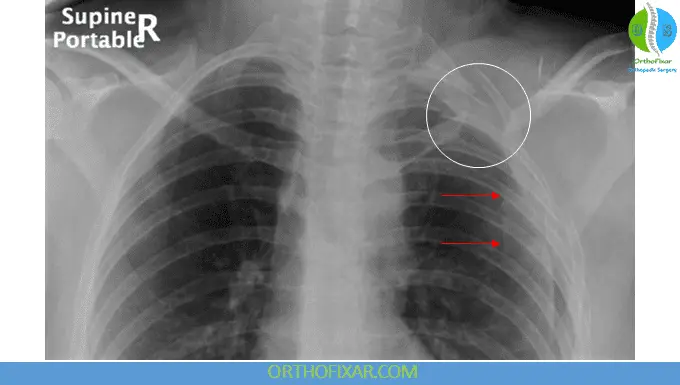

Chest radiograph (nonrotated) is key:

- Shows lateral displacement of the scapula compared to the contralateral side

- This finding is considered diagnostic

- Lateral scapular displacement on chest X-ray is diagnostic.